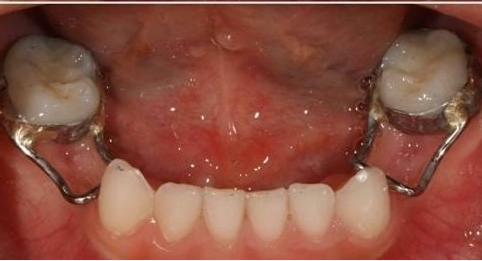

1、预防矫治。采用各种预防措施来防止各种错颌畸形的发生,是预防矫治的主要内容。儿童出生萌芽后要定期进行口腔检查,早期发现问题早期防止,如龋的早期治疗、口腔不良习惯的早期破除、乳牙早失的缺隙保持以及滞留牙、多生牙的及时拔除等,使通过这些预防可防止错颌畸形的发生。

乳牙早失导致拥挤

间隙保持器为“新牙”萌出保留空间

乳磨牙缺损较大

预成冠修复后